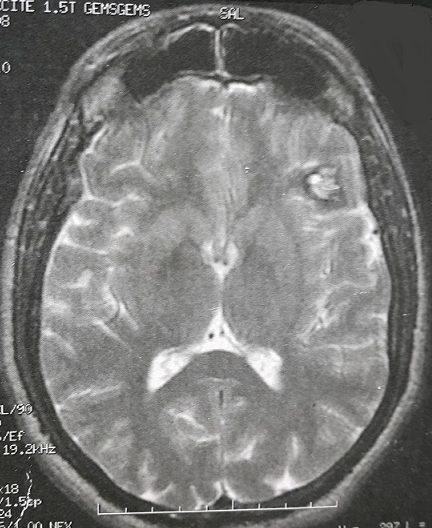

Image en popcorn cérébrale

Les cavernomes cérébraux sont des lésions vasculaires définies par la présence de capillaires malformés sans interposition de tissu nerveux. Ce sont des lésions relativement rares (0,1à 0,5% de la population générale dont moins de 5% sont symptomatiques), la symptomatologie clinique est dominée par l'hémorragie et l'épilepsie et dépend aussi de la localisation. L'IRM cérébral est l'examen de référence pour le diagnostic, l'approche thérapeutique et le suivi. Nous rapportons ici l'observation clinique d'un jeune homme de 27 ans, sans antécédents, qui a présenté deux crises convulsives généralisées à une semaine d'intervalle. L'examen clinique a été normal. L'IRM cérébrale a objectivé une lésion frontale gauche avec aspect typique en pop corn ou poivre et sel associant hyper signal (saignement récent ou calcifications) et hypo signal (dépôt d'hémosidérine=saignement ancien) sur les séquences pondérées T2. Le patient a été mis sous traitement antiépileptique a base d'acide valproïque avec contrôle total des crises.